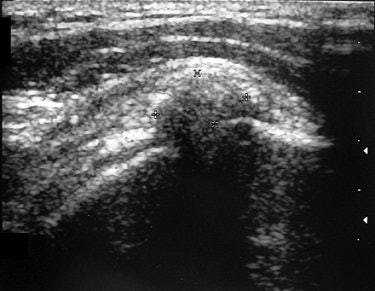

| Same patient as above. Note changes in sonogram of calcification after percutaneous treatment. Ten weeks after treatment, volume of calcification has been considerably reduced and no acoustic shadow is seen. Del Cura JL, Torre I, Zabala R, Legórburu A, "Sonographically Guided Percutaneous Needle Lavage in Calcific Tendinitis of the Shoulder: Short- and Long-Term Results" (AJR 2007; 189:W128-W134). |

At one-year follow-up, post-treatment radiography indicated that 78.1% of the shoulders showed no sign of calcifications. Before treatment, 58.2% of the cases had strong acoustic shadows on sonography, but after one year only 1.6% showed a strong acoustic shadow. A little over half (50.7%) of the shoulders were completely free of symptoms, the authors reported. These patients also reported lower scores on the Shoulder Pain and Disability Index.